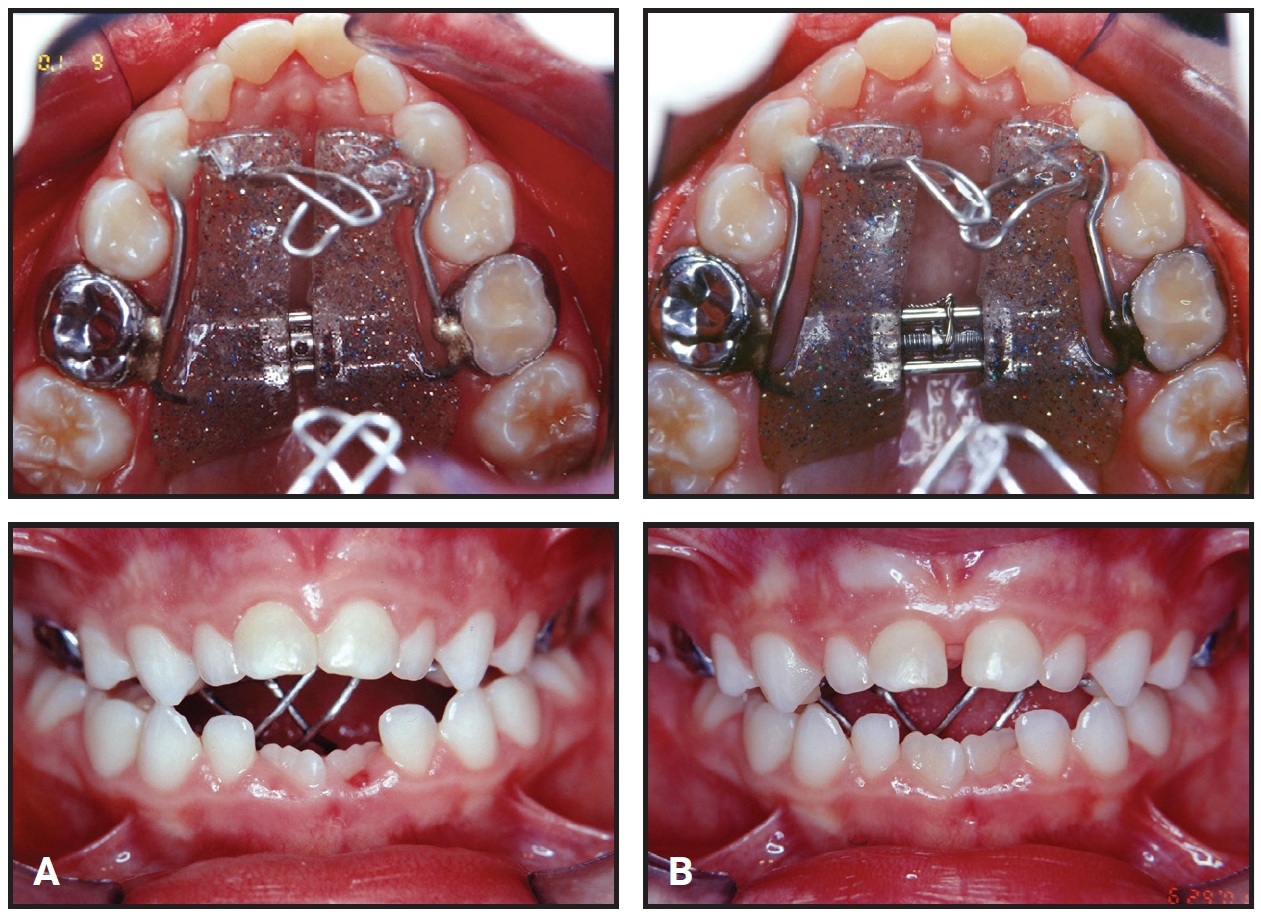

Phase II was initiated 36 months after the completion of Phase I (Fig. 3).

Fig. 3 Patient at start of Phase II, 36 months after Phase I completion.

An orthopedic device was used together with a combination-pull headgear to control vertical mandibular growth. This extraoral traction reduced the anteroposterior maxillomandibular discrepancy by promoting counterclockwise rotation of the mandible and restricting horizontal growth of the maxilla (Table 1).

After extraction of the upper first premolars and lower second deciduous molars on both sides, corrective orthodontic treatment was initiated with standard .022" × .028" edgewise appliances. Leveling and alignment occurred over 16 months on a sequence of .014" to .020" stainless steel archwires. To close the extraction spaces, looped .018" × .025" and .019" × .025" stainless steel archwires were used to retract the upper canines and incisors and the lower premolars, canines, and incisors. The patient wore the headgear nightly during this phase, which took 23 months. To improve intercuspation in the final stages, Class II intermaxillary elastics (¼") and vertical elastics (3⁄16") were worn bilaterally, along with intermaxillary elastics (¼") in the anterior region.